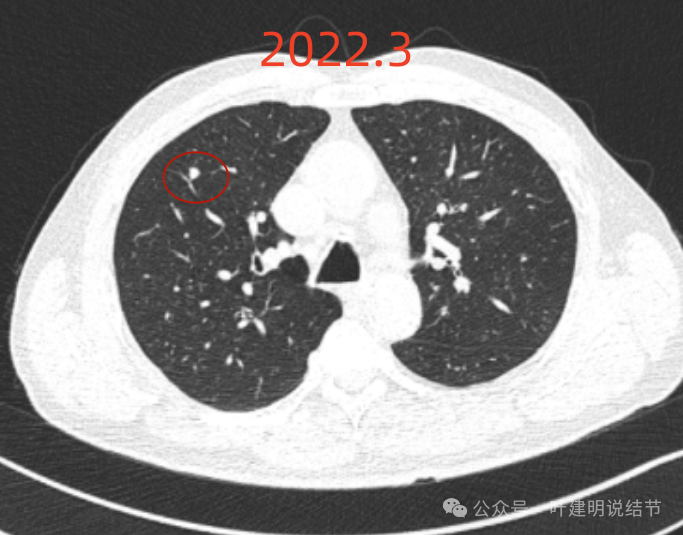

我们先来看2022年3月主要病灶的影像:

右上叶结节实性,密度高,边缘平整,轮廓清楚,像良性些。

右下似见微小结节,实性,与边上小血管截面不太好区分,过小没什么临床意义,能随访。

左下胸膜下实性结节,轮廓稍模糊,密度较高,边缘较光,像淋巴结些,能随访。